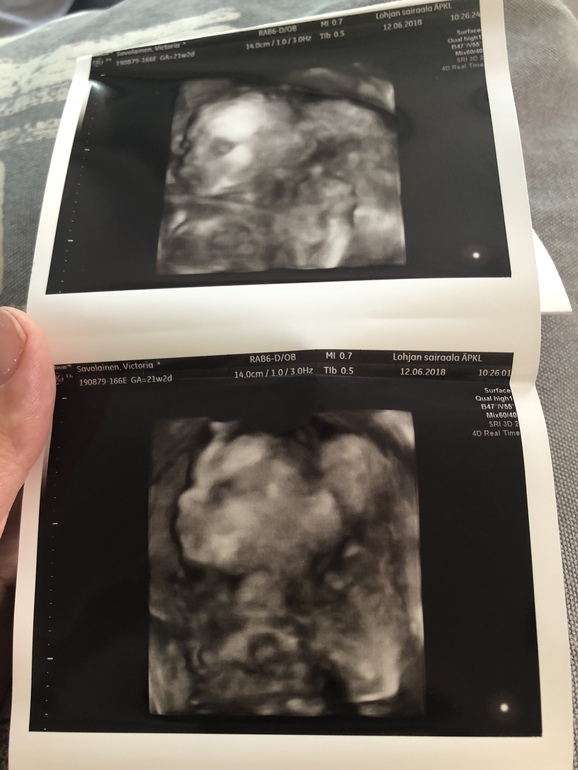

Срок 21+2 все в полном порядке, все соответствует сроку:) вес 396гр. И мальчика нам подтвердили🙈😍💙💙💙 люлька с синим капюшоном уже дома , одежду начала покупать , я в счастливом шоке! Также не может н

радовать что я худею потихоньку , добеременности 95,7 сейчас 90,7:) хочу ещё :) Ну и фоточек несколько , т к плацента по передней стенке Было очень трудно сфотать